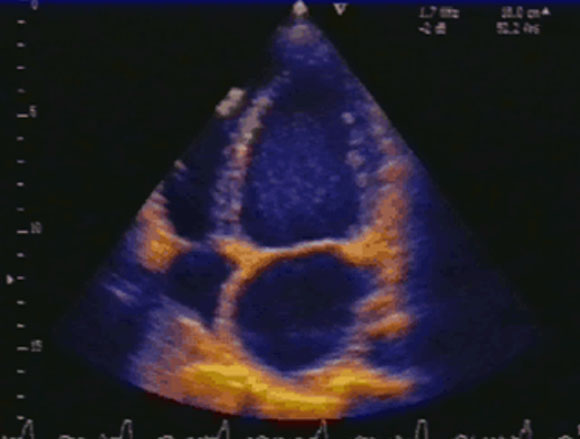

- 7 - Echocardiographie - Doppler